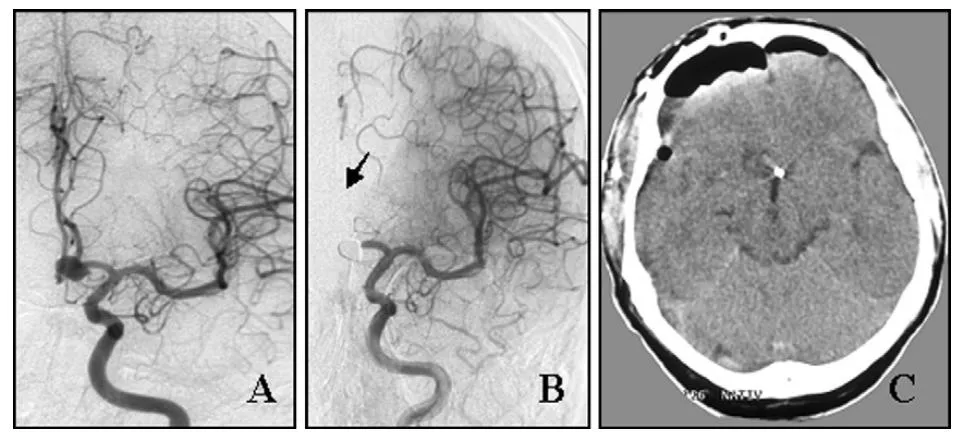

两个典型病例能说明问题。一位58岁男性,前交通动脉动脉瘤栓塞术后即刻造影发现左侧大脑前动脉A2段闭塞,为预防脑梗死,急诊开颅取出弹簧圈并完成血栓取栓,恢复血管通畅,最终以动脉瘤夹完成夹闭,术后一个月恢复日常活动。

(A)栓塞术前血管造影显示左侧前交通动脉动脉瘤。

(B)栓塞术后即刻血管造影显示动脉瘤致密栓塞,左侧大脑前动脉A2段闭塞。

(C)术后CT扫描未见大脑半球梗死。

另一位37岁女性,小脑后下动脉动脉瘤介入治疗中弹簧圈被迫撤出,随后即刻造影提示小脑后下动脉血栓形成管腔闭塞,急诊经远外侧入路同期完成血管再通和动脉瘤夹闭,术后3个月恢复工作。

(A)左侧椎动脉数字减影血管造影(DSA)显示椎动脉 - 小脑后下动脉动脉瘤。

(B)栓塞术后即刻血管造影未见左侧小脑后下动脉显影,原因为动脉瘤内血栓形成并蔓延至左侧小脑后下动脉近端(箭头所示)。

(C)动脉瘤夹闭并血栓切除术后血管造影,动脉瘤已完全闭塞。

(D)弹簧圈栓塞失败后,动脉瘤瘤顶被完整血栓填塞扩张。